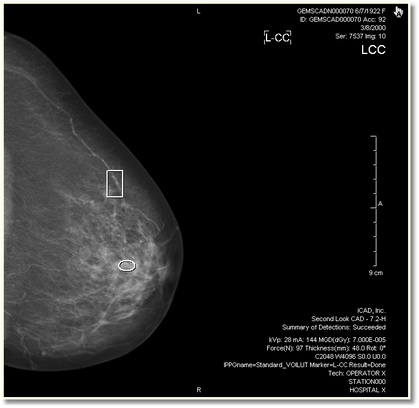

When CAD has been activated from the toolbar, the CAD information will appear as annotations and the markers will appear on top of the image.

There are three types of CAD markers that shows the location of abnormalities:

| Circle/elliptical markers indicate dense areas. | |

| Rectangular markers indicate area that may have micro calcification. | |